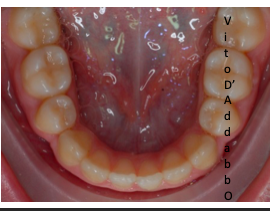

prima